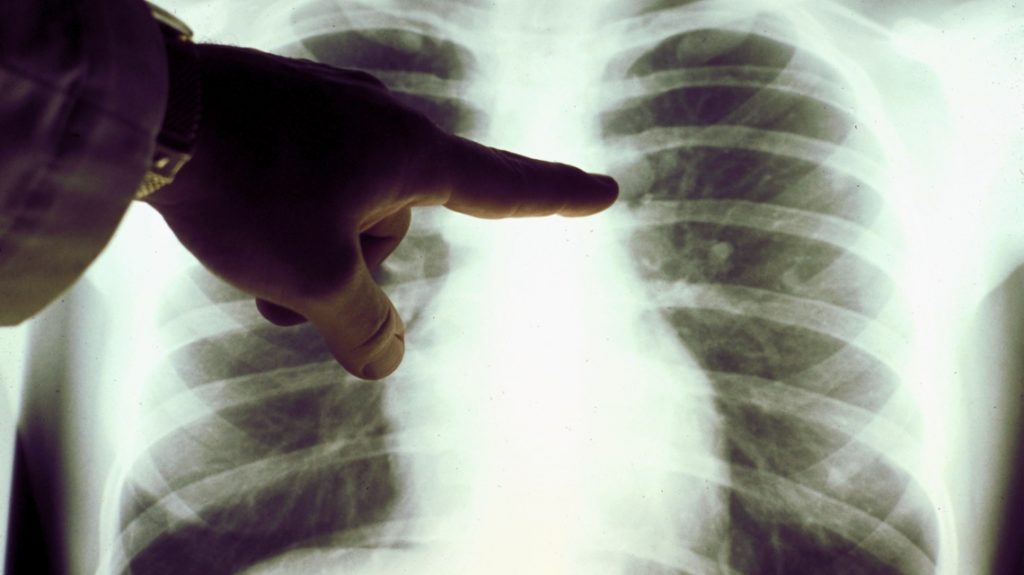

En el Día Internacional del Cáncer de Pulmón, que se conmemora el 17 de noviembre, el Ministerio de Salud recuerda a la población que el Cáncer de Pulmón es un tumor que afecta a las células de ese órgano vital y que representa el 10 por ciento de los cánceres diagnosticados en Argentina cada año. 8 de cada 10 personas que tienen cáncer de pulmón son causadas por el hábito de fumar y solo en nuestra provincia mueren unas 300 personas al año por este tipo de cáncer, recordó Salud.

En la provincia de Santa Fe el cáncer de pulmón es la primera causa de muerte por cáncer en hombres, remarcó la directora de la Agencia de Control del Cáncer del Ministerio de Salud, Graciela López de Degani. Si bien hay mayores índices de mortalidad en hombres, en mujeres el número fue creciendo en paralelo con el consumo de tabaco y estilos de vida.

“El cáncer de pulmón es un tumor con alta mortalidad, en aumento sobre todo en mujeres”, contó y graficó López de Degani e insistió que “esto es una tendencia que está ocurriendo en el mundo y que debemos prestar especial atención en mejorar nuestros estilos de vida y sobre todo dejar de fumar”.